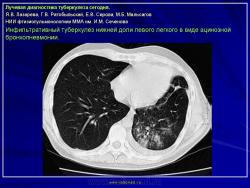

Лучевая диагностика туберкулеза сегодня

Я.В. Лазарева, Г.В. Ратобыльский, Е.В. Серова, М.Б. Мальсагов

НИИ фтизиопульмонологиии ММА им. И.М. Сеченова